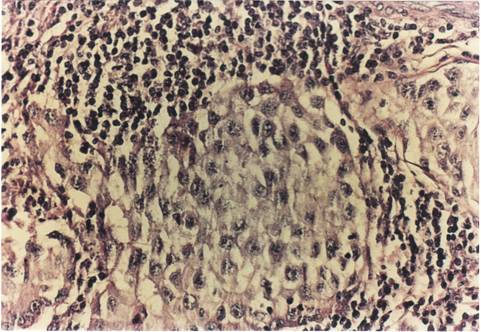

Criterii microscopice de diagnosticare a cancerului mamar

Pentru examenul histopatologic piesele de mamectomie sunt prelucrate prin imparafinare si colorate cu Hematoxilina-Eozina sau, pentru observarea mai buna a tesutului conjunctiv, cu Van Gieson.

Colorarea se realizeaza pentru observarea difertiata a structurilor celulare (colorantul adera selectiv la structurile celulare, colorandu-le diferit). Hematoxilin-eozina contine hematoxilina si eozina (colorant acid anionic). Colorantul se oxideaza la aer in timp indelungat sau chimic, cu iodura de sodiu. Colorantul determina culoarea roz a citoplasmei celulare, nucleul bazofil (albastru-violet), heterocromatina se coloreaza intens, dar nu si invelisul nuclear, nucleolii apar foarte colorati si in citoplasma se observa granule albastru- violacee, ce sunt ribozomii, care contin ARN.

Pe preparate colorate, la microscopul optic se observa urmatoarele imagini :